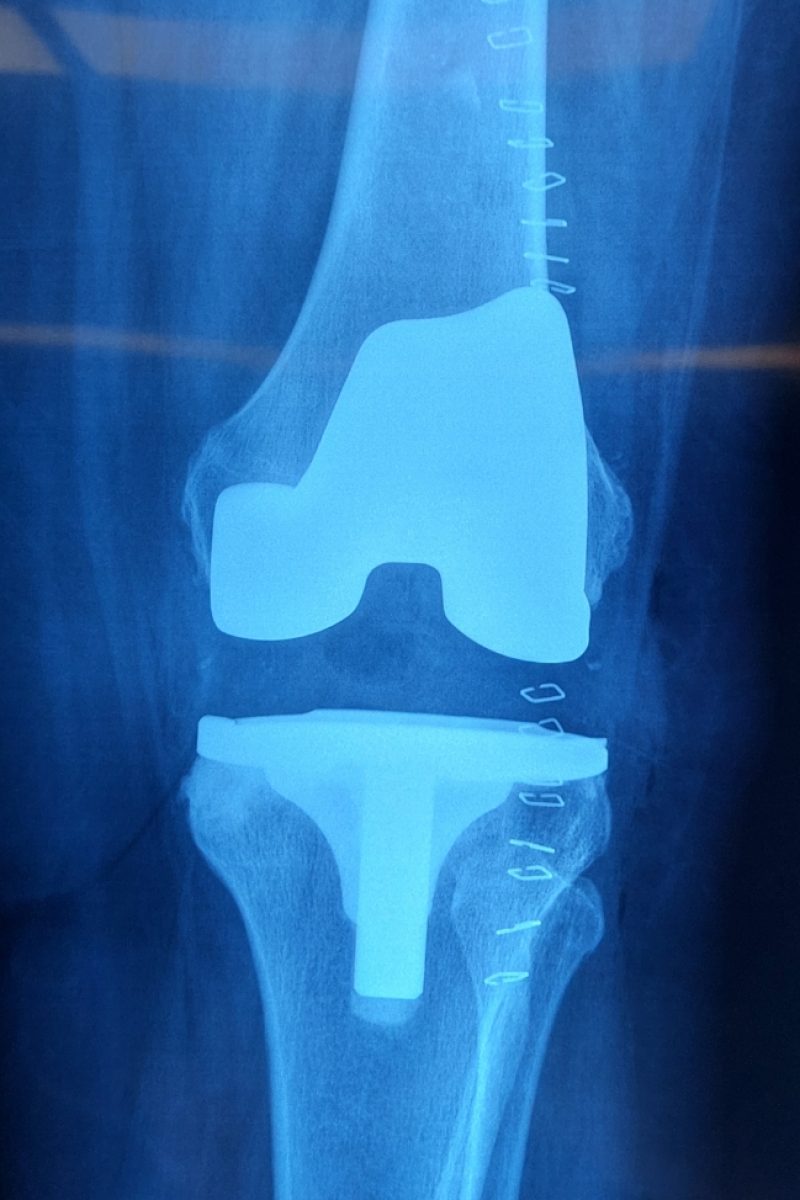

Total Knee Replacement or knee arthroplasty is a surgery in which doctors replace damaged tissues of the knee with artificial implants. This helps reduce pain and improve movement. In Pakistan, the methods include total and partial Knee Replacement. Only a few Orthopedic Doctors perform minimally invasive Knee Surgery. Dr. Imran Salim Malik is the top Orthopedic Surgeon in Lahore who performs total Knee Replacement using advanced minimally invasive procedures that not only reduce post surgical infection risks but also improves mobility.

Total Knee Replacement with a small cut causes less muscle damage, which reduces the risk of post-surgery infections. Additionally, Dr. Imran Salim only uses quality MRI-compatible titanium, cobalt chrome implants, ensuring extended durability and smooth recovery.